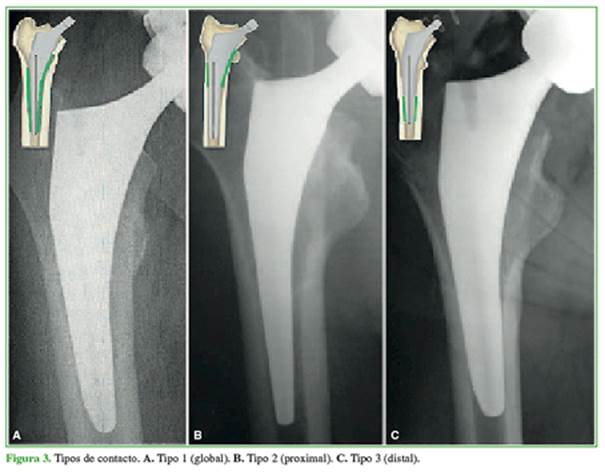

Con dichas medidas, se clasificó el contacto en: tipo 1 (global), cuando hay una fijación proximal y distal (la diferencia entre la brecha proximal y la distal es de 2 mm o menos), tipo 2 (proximal), cuando la fijación es solo proximal, y tipo 3 (distal) cuando el contacto es solo distal (Figura 3).3

Se han publicado artículos sobre la adaptación del tallo femoral y sus complicaciones, como ausencia de osteo-integración, hundimiento, fracturas periprotésicas intraoperatorias o en el posoperatorio inmediato, dolor residual de muslo, etc.5-8 La geometría del implante, el material de fabricación, la edad y la calidad ósea del huésped, la técnica de colocación y la relación del diseño del implante-fémur son factores señalados en estos reportes.1,9,10 A fin de disminuir el micromovimiento y facilitar la osteointegración, es necesario el contacto íntimo entre el hueso cortical y el implante.11 En nuestro estudio, observamos un predominio en el tipo de contacto global (tipo 1) en el grupo 2 del 88% comparado con el 60% en el grupo 1.